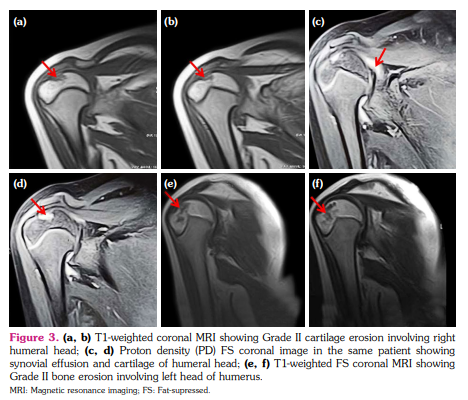

a) Synovial hypertrophy score: Thirteen (40.6%) joints in nine patients revealed synovial hypertrophy with a mean grade score of 0.7±0.9 (Figure 1 a, b). Five joints had Grade I and eight joints had Grade II synovial hypertrophy (Figure 2a). The number of joints with synovial hypertrophy in sJIA, ERA, and undifferentiated JIA were seven (53.8%), four (30.7%), and two (15.3%) joints, respectively.

b) BME score: Twenty-one (65.6%) joints in 13 patients revealed BME with a mean grade score of 1.1±1.0 (Figure 1c, d). The number of joints which had Grade I, II and III BME scores were 11, seven, and three, respectively (Figure 2a). The number of joints with BME in sJIA, ERA, and undifferentiated JIA was 13 (61.9%), five (23.8%), and three (14.2%) joints, respectively. Of these 21 joints, only two joints revealed BME with no other findings and the rest 19 joints showed synovial effusion or one or the other MRI parameter of joint inflammation. There was no statistically significant difference in the occurrence of BME in sJIA subset versus the rest of the JIA subsets (p=0.823).